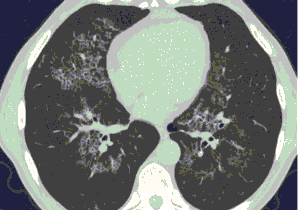

4.3. ЛУЧЕВАЯ ДИАГНОСТИКА COVID-19

Методы лучевой диагностики применяют для выявления COVID-19 пневмоний, их осложнений, дифференциальной диагностики с другими заболеваниями легких, а также для определения степени выраженности и динамики изменений, оценки эффективности проводимой терапии.

Лучевые методы также необходимы для выявления и оценки характера патологических изменений в других анатомических областях и как средства контроля для инвазивных (интервенционных) медицинских вмешательств.

К методам лучевой диагностики патологии ОГК пациентов с предполагаемой/установленной COVID-19 пневмонией относят:

- Обзорную рентгенографию легких (РГ),

- Компьютерную томографию легких (КТ),

- Ультразвуковое исследование легких и плевральных полостей (УЗИ).

Стандартная РГ имеет низкую чувствительность в выявлении начальных изменений в первые дни заболевания и не может применяться для ранней диагностики. Информативность РГ повышается с увеличением длительности течения пневмонии. Рентгенография с использованием передвижных (палатных) аппаратов является основным методом лучевой диагностики патологии ОГК в ОРИТ. Применение передвижного (палатного) аппарата оправдано и для проведения обычных РГ исследований в рентгеновском кабинете. В стационарных условиях относительным преимуществом РГ в сравнении с КТ являются большая пропускная способность. Метод позволяет уверенно выявлять тяжелые формы пневмоний и отек легких различной природы, которые требуют госпитализации, в том числе направления в ОРИТ.

КТ имеет высокую чувствительность в выявлении изменений в легких, характерных для COVID-19. Применение КТ целесообразно для первичной оценки состояния ОГК у пациентов с тяжелыми прогрессирующими формами заболевания, а также для дифференциальной диагностики выявленных изменений и оценки динамики процесса. КТ позволяет выявить характерные изменения в легких у пациентов с COVID-19 еще до появления положительных лабораторных тестов на инфекцию с помощью МАНК. В то же время, КТ выявляет изменения легких у значительного числа пациентов с бессимптомной и легкой формами заболевания, которым не требуется госпитализация. Результаты КТ в этих случаях не влияют на тактику лечения и прогноз заболевания при наличии лабораторного подтверждения COVID-19. Поэтому массовое применение КТ для скрининга асимптомных и легких форм болезни не рекомендуется. При первичном обращении пациента с подозрением на COVID-19 рекомендуется назначать КТ только при наличии клинических и инструментальных признаков дыхательной недостаточности (SpO2 < 95%, ЧДД > 22).

15. Рекомендации по формированию описаний и оценке изменений в легких и ОГК при имеющейся/подозреваемой пневмонии COVID-19 представлены в Приложении 1.